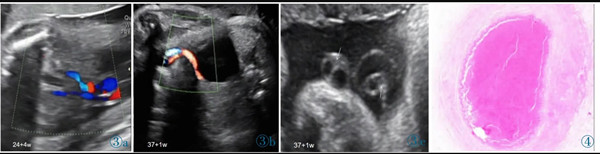

11 例中孕期超聲均可見2 條UA(膀胱水平橫切面顯示2 條UA 血流信號),超聲最后一次提示可見2 條UA 的平均孕周為(31.2±3.1)周。11 例超聲首次提示UA 數(shù)目異常(表現(xiàn)為膀胱水平橫切面UA彩色多普勒僅顯示1 條UA 及血流信號,另一側(cè)血流信號消失)的平均孕周為(36.7±2.8)周,6 例(54.4%)為膀胱左側(cè)血流信號消失,5 例(45.5%)為膀胱右側(cè)血流信號消失。7 例(63.6%)孕晚期超聲首次即提示單條UAT,這7 例臍帶游離段橫切面二維灰階圖像均顯示3 個管腔結(jié)構(gòu),其中1 條UA 內(nèi)可見稍高回聲填充且血流信號消失(圖1);1 例(9.1%)在孕34+4周提示單臍動脈,在孕37 周超聲隨訪中糾正診斷為單條UAT,因超聲提示臍帶高度螺旋,且在臍帶橫切面下見臍靜脈呈“C 形”包繞2條UA,1 條UA 內(nèi)存在血栓回聲(圖2),該病例同時合并胎兒生長受限;3 例(27.3%)整個孕期均提示單臍動脈,回顧其既往中孕期超聲均見2 條UA,晚孕期超聲發(fā)現(xiàn)1 條UA 內(nèi)存在血栓回聲(圖3)。

圖3 誤診為單臍動脈病例的超聲圖像。圖3a:孕24+4 周,膀胱兩側(cè)均可見UA 血流信號;圖3b:孕37+1 周,膀胱一側(cè)UA 血流信號消失;圖3c:臍帶橫切面見臍靜脈呈“C 形”包繞2 條UA,箭頭所示其中1 條UA 管腔細小,內(nèi)為稍高回聲(血栓)填充。圖4 臍帶病理(HE 染色)。UA 內(nèi)見血栓形成,管壁彈力纖維梗死。Figure 3.Ultrasonography misdiagnosed as single umbilical artery.Figure 3a: At 24+4 weeks,the blood flow of two UAs is seen in both sides of bladder.Figure 3b: At 37+1 weeks,only one UA is seen in the level of bladder.Figure 3c: In the cross section of umbilical cord,two UAs are surrounded by umbilical vein.As indicated by the arrows,one UA has smaller lumen which is filled with a slightly higher echo(thrombi).Figure 4.The pathological finding of umbilical cord (HE stain).The UA lumen is filled with thrombi.The necrosis of elastic fibers are found in arterial wall.

產(chǎn)前超聲診斷單條UAT 的8 例均急診收住院。其中,6 例入院后行急診剖宮產(chǎn)分娩;1 例入院后臨產(chǎn),產(chǎn)程進展迅速,在急診剖宮產(chǎn)術(shù)前準備期間經(jīng)陰道分娩;1 例在孕29+1周超聲提示單條UAT,因考慮孕周小早產(chǎn)兒預(yù)后差,同時孕婦拒絕急診剖宮產(chǎn),出院后在嚴密監(jiān)測下期待至孕足月,最終孕婦堅決要求孕38+2周擇期剖宮產(chǎn)分娩。

11 例均為活產(chǎn),男8 例,女3 例,足月10 例,早產(chǎn)1 例。新生兒出生體質(zhì)量(2 855±440)g,1 例(9.1%)為小于胎齡兒。3 例(27.2%)羊水糞染,1 例(9.1%)發(fā)生新生兒窒息(輕度)。9 例轉(zhuǎn)新生兒重癥監(jiān)護室,其中3 例轉(zhuǎn)科后情況穩(wěn)定;2 例因產(chǎn)前超聲發(fā)現(xiàn)心臟發(fā)育異常(分別為室間隔缺損和完全性大動脈轉(zhuǎn)位)轉(zhuǎn)科;4 例轉(zhuǎn)科后均出現(xiàn)與缺氧相關(guān)病理情況,經(jīng)治療后情況穩(wěn)定后出院。

產(chǎn)時肉眼可見11 例臍帶長度均正常,其中4 例(36.4%)臍帶高度螺旋,1 例(9.1%)帆狀胎盤。7 例產(chǎn)時病歷描述可見1 條UA 外觀全程/部分呈暗紅色,1 例UA 部分呈土黃色,橫斷面均可見血栓形成。3 例病歷資料中未描述臍帶外觀。病理結(jié)果提示11 例臍帶橫斷面均提示有2 條UA,鏡下所見其中1 條UA 內(nèi)血栓形成(圖4)。